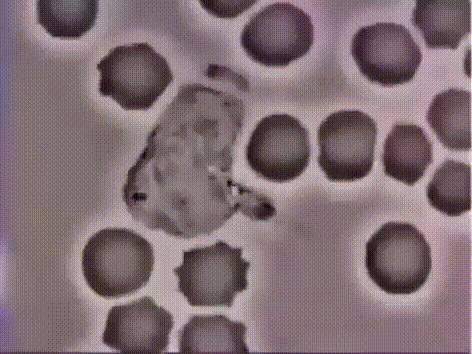

박테리아를 따라가는 백혈구